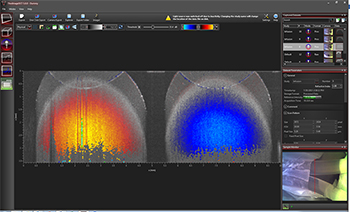

Click to Enlarge

Figure 116W Speckle variance measurement showing blood vessels of a mouse brain.

Speckle Variance Mode

The speckle variance imaging mode is an acquisition mode which uses the variance of speckle noise to calculate angiographic images. It can be used to visualize three dimensional vessel trees without requiring significant blood flow and without requiring a specific acquisition speed window. The speckle variance data can be overlaid on top of intensity pictures providing morphological information. Different color maps can be used to display the multimodal pictures.